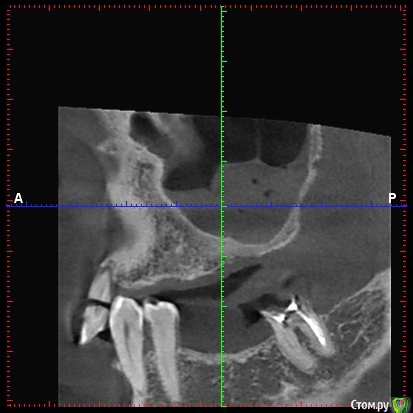

DenisV Опубликовано 11 декабря, 2017 Поделиться Опубликовано 11 декабря, 2017 Доктора, пациент обратился с целью установки имплантатов. На клКТ обнаружено затенение пазухи, отправлен к ЛОР на консультацию. Что это? синусит? ретенционка? Ссылка на комментарий

Большой Зеленый Опубликовано 12 декабря, 2017 Поделиться Опубликовано 12 декабря, 2017 Гайморит . 5 Ссылка на комментарий

Paganini Опубликовано 12 декабря, 2017 Поделиться Опубликовано 12 декабря, 2017 (изменено) Это синусит. И жалоб нет? Изменено 12 декабря, 2017 пользователем Paganini Ссылка на комментарий

колесников Опубликовано 12 декабря, 2017 Поделиться Опубликовано 12 декабря, 2017 Пузырьки газа в жидкости. Ссылка на комментарий